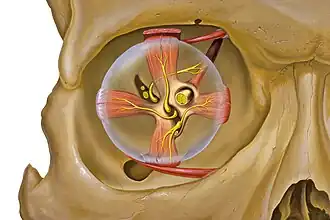

Extraocular muscles

Each eye has seven extraocular muscles located in its orbit.[7] Six of these muscles control the eye movements, the seventh controls the movement of the upper eyelid. The six muscles are four recti muscles: the lateral rectus, the medial rectus, the inferior rectus, and the superior rectus; and two oblique muscles: the inferior oblique, and the superior oblique. The seventh muscle is the levator palpebrae superioris muscle. When the muscles exert different tensions, a torque is exerted on the globe that causes it to turn, in almost pure rotation, with only about one millimeter of translation.[8] Thus, the eye can be considered as undergoing rotations about a single point in the centre of the eye.

Eye and orbit anatomy with motor nerves

Eye and orbit anatomy with motor nerves -

Normal anatomy of the human eye and orbit, anterior view

Normal anatomy of the human eye and orbit, anterior view